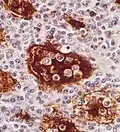

Micrograph showing emperipolesis in a case of Rosai-Dorfman disease. H&E stain.

Emperipolesis is the presence of an intact cell within the cytoplasm of another cell.[1] It is derived from Greek (en is inside, peripoleomai is go round).[2] Emperipolesis is an uncommon biological process, and can be physiological or pathological.[3]

2. Engulfment of inflammatory cells by histiocytes, which is a hallmark of Rosai-Dorfman disease[5]